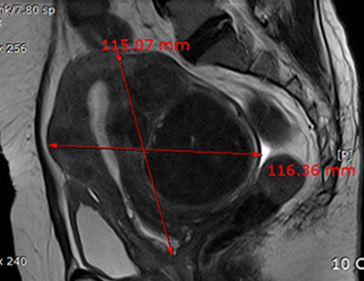

자궁근종 치료 사례

• 시술 전

시술 후